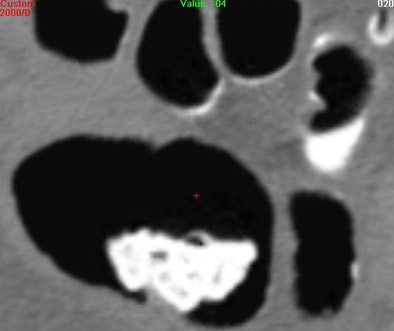

| Three-dimensional endoluminal view (above) and 2D MPR (below) of a patient who underwent prepless VC with the aid of a NutraPrep (E-Z-EM) low-residue diet for two days before imaging, and 120 cc of MD-GastroView (Mallinckrodt, Hazelwood, MO) iodinated oral contrast the night before the exam. |

Instead of 3D, Choi said his group uses a magnified 2D multiplanar reconstructed (MPR) view of the colon wall that is orthogonal to the centerline of the colon, read, like 3D, on the Viatronix workstation.

With the magnified 2D, "you see 100% of the colon surface with simple fly-through, and it's easier to differentiate polyps and folds compared to looking at, say, a magnified axial view," he said. "However it's more difficult to (determine) the absolute location of the polyps."

Overall magnified 2D MPR view picks up polyps fairly easily, Choi said, and for individual lesions a 3D view can be used for troubleshooting. The new study will provide more insight into the 2D reading method.